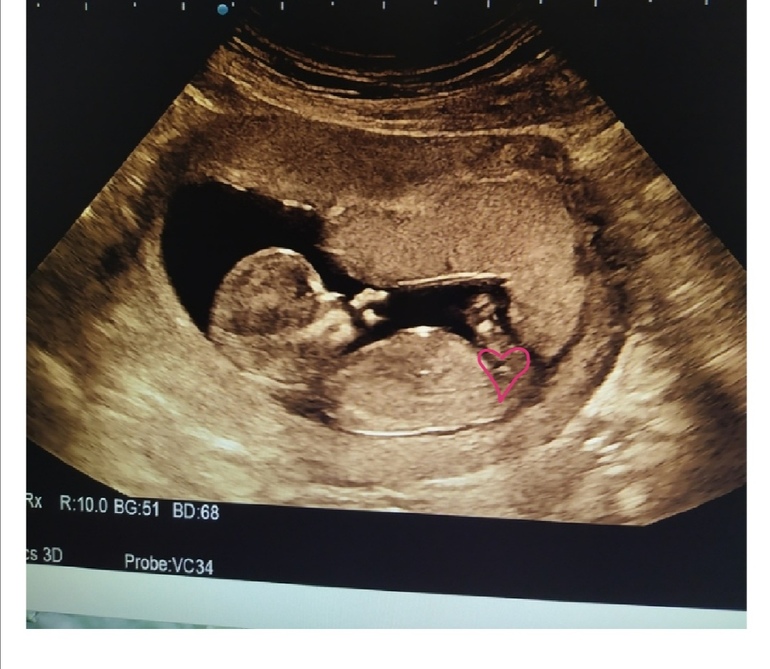

Пол малышаВрач даже предполагать пол не стала, но мне прям не терпится,хотя от этого ничего не изменится обсалютно, ребенок самый родной и любимый,может у кого глаз наметан,я в этом вообще валенок и даже смотреть не знаю куда,видела девочки как то по половому бугорку смотрят,на моем что-то непонятно как то

Посему то мне кажется что девочка...половой бугорок как то не к верху как у мальчишек

Где тут народ бугорок увидел не пойму. Его на фото нет, закрыт ногой